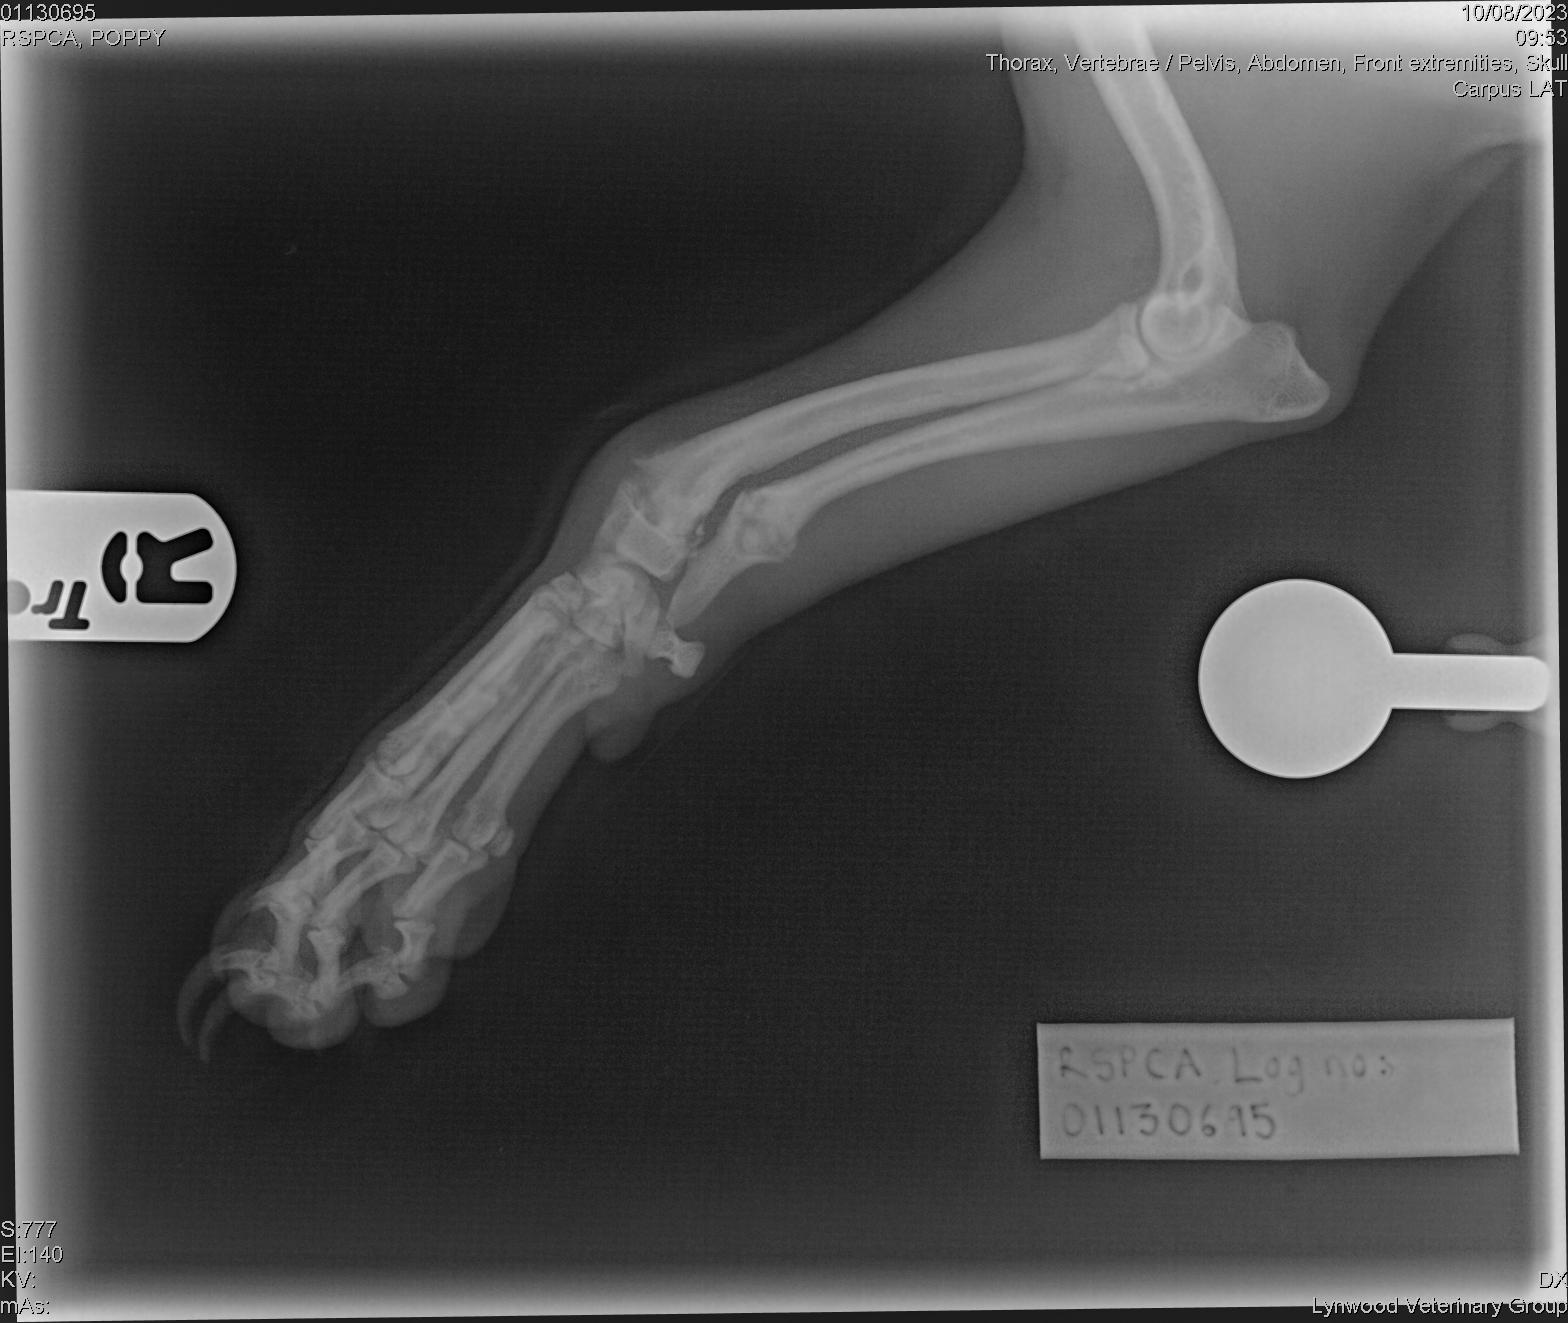

She was rushed for urgent veterinary treatment by the RSPCA where examinations and X-rays found further injuries.

As well as the untreated broken back leg she had two fractures to her right front leg which had started to heal and other historic injuries, including three fractured ribs as well as skin wounds, an amputated ear tip and a cut to her tongue which had since healed.

The vet concluded these injuries were non-accidental and had been caused on different occasions so an investigation was launched by RSPCA Inspector Patrick Bailey in August 2023.

He said: “It was so sad when I first saw Poppy – she was so happy and lovely – but because she had a fracture to her back left leg and two to her right front leg, to move and balance her weight she had to choose which fractured leg to walk on.

Some of Poppy’s injuries Picture: RSPCA